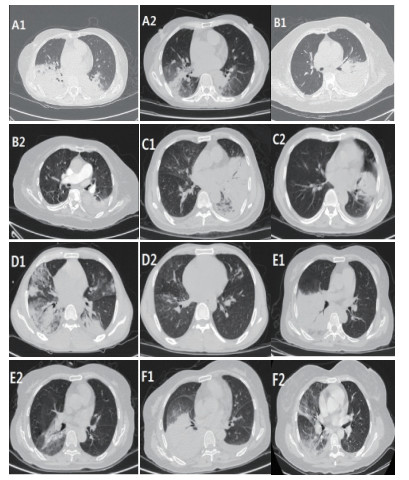

4例患者白细胞正常,2例患者出现升高;4例患者中性粒细胞比例升高,2例正常;5例患者ESR不同程度升高(32~88 mm/h);6例患者Hs-CRP升高明显;3例PCT升高明显,3例轻度升高;6例患者均出现转氨酶异常;3例患者出现心功能不全,4例出现轻度心肌损伤;1例患者出现肾功能不全。5例患者CD3+、CD4+细胞数减少,表现为细胞免疫抑制。患者胸部影像学检查结果表现为渗出性病变,实变为主,可累及多个肺叶,肺下叶受累较常见,病灶进展迅速,后期可出现少许胸腔积液,见表 1、2及图 1。

| A1、A2;B1、B2;C1、C2;D1、D2;E1、E2;F1、F2分别为病例1~6患者治疗前后胸部CT变化情况,患者表现为大片状实变影,经治疗后胸部CT可见病灶明显吸收。 图 1 6例患者胸部CT表现 |

鹦鹉热本质上是一种全身性疾病,以呼吸系统感染为主,也可累及肝脏、肾脏、血液、循环及中枢神经等系统,导致多器官功能不全[9-10]。Chen等[6]报道的9例重症鹦鹉热肺炎患者中均出现畏寒发热、咳嗽、乏力及呼吸衰竭等症状,多个患者出现头晕、肌痛并发展为脓毒血症;实验室检查提示白细胞正常或轻度升高,中性粒细胞比例升高,CRP、PCT升高明显,部分患者出现心肌酶、肝酶升高,这与本研究报道的结果基本一致。患者均表现有高热及CRP明显升高,但白细胞数正常或轻度升高,这是与细菌性肺炎鉴别的一个重要特征。影像学方面,该疾病尚缺乏特异性表现,胸部X线最常见表现为单个下肺叶改变,胸部CT显示实变结节与周围磨玻璃改变[1]。本研究所报道的6例病例胸部CT均以实变为主要征象,多为大片实变,以肺下叶受累明显,与Coutts等[11]、Kong等[12]报道相一致。而Gu等[7]报道的5例鹦鹉热衣原体肺炎中2例以肺下叶实变为主,2例以右肺上叶实变为主,1例起初以右上肺实变为主,后病情加重,胸部CT显示双肺弥漫病灶,以双下肺大片实变为主。出现以上差异,可能与纳入研究病例的病情严重程度有关。